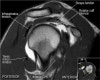

어깨 관절의 MRI 단면영상

- Coronal section

1) Supraspinatus, Inpraspinatus tendon

2) AC joint

3) Labrum(superior, inferior)

4) Biceps anchor, Inferior GHL, Axillary recess

5) GH joint cartilage

6) Osseous structure

7) Deltoid